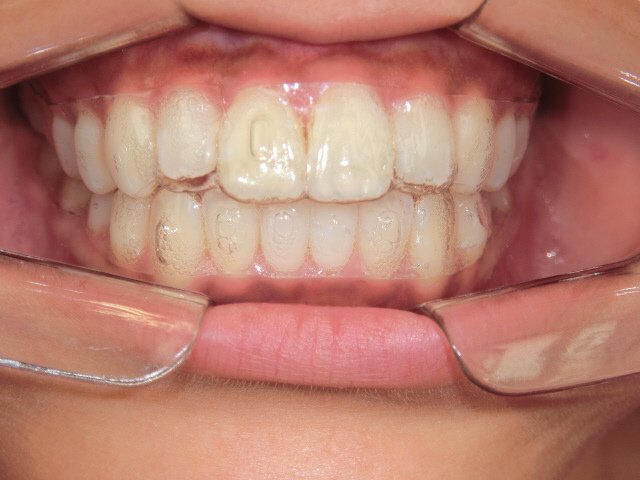

左上は、スマイルトゥルー(アライナー矯正装置)を装着した状態です。従来のワイヤー矯正と比較して目立ちにくいのが特徴です。右上の写真は装置そのもので、透明性が高く、会話距離ではほとんど気づかれないと考えられます。